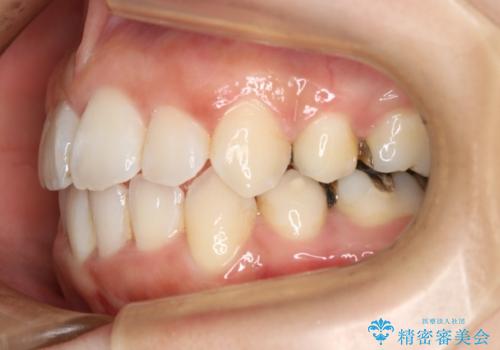

- 歯のガタつきと出っ歯が気になるので矯正治療を希望し来院された患者様です。

上下顎とも歯を並べられるスペースが無く、口元を下げたいというご希望だったので、抜歯とワイヤー矯正を併用した治療を計画しました。

抜歯スペースを利用し口元を大きく下げることが出来ました。